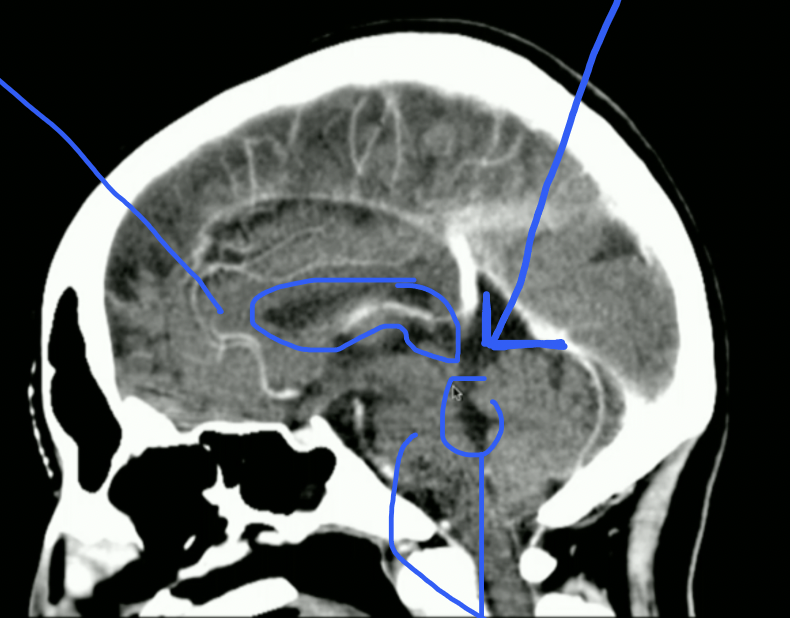

<p>What is highlighted?</p>

What is highlighted?

• 3rd Ventricle

• CSF then goes to Cerebral Aqueduct

<p>What is Top + Bottom Circle + Arrow?</p>

What is Top + Bottom Circle + Arrow?

• Top: 3rd Ventricle

• Bottom: 4th Ventricle

• Arrow: Cerebral Aqueduct

<p>What Part of Brain Stem?</p>

What Part of Brain Stem?

• Pons

• Look for Basilar Groove

• Mid-brain

• Look for Cerebral Aqueduct

<p>What Part of Brainstem?</p>

What Part of Brainstem?

• Medulla Oblungata

• Stops at Foramen Magnum